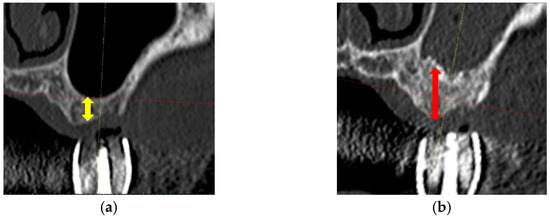

2.4.1. SFE Evaluation in a Clinical Trial

- Nakagawa, T.; Kudoh, K.; Fukuda, N.; Kasugai, S.; Tachikawa, N.; Koyano, K.; Matsushita, Y.; Sasaki, M.; Ishikawa, K.; Miyamoto, Y. Application of low-crystalline carbonate apatite granules in 2-stage sinus floor augmentation: A prospective clinical trial and histomorphometric evaluation. J. Periodontal Implant. Sci. 2019, 49, 382–396. [Google Scholar] [CrossRef] [PubMed]